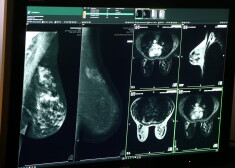

“RAKUS ir viss nepieciešamais tehnoloģiskais nodrošinājums, lai ārstētu (diagnosticētu, monitorētu un uzturētu pacientu dzīvības funkcijas) Covid-19 pacientus. Lai gan epidemioloģiskās drošības apsvērumu dēļ neesam varējuši bieži aicināt žurnālistus skatīt intensīvās terapijas palātas, kur ārstējas liela daļa Covid-19 pacientu, tomēr priekštatu var gūt aplūkojot aģentūras LETA fotogrāfa Edija Pālena fotogrāfijas, kas bija publicētas mūsu sociālajos tīklos, kā arī ieguva ārkārtīgi plašu rezonansi ne tikai Latvijas medijos, bet arī ārzemju ziņu portālos,” iepazīstoties ar Krievijas medijos atrakstītajiem Putina apgalvojumiem, taču nekomentējot konkrēti minētās personas ārstēšanu, pauda RAKUS pārstāve.

Austrumu slimnīcā prezentē jaunu magnētiskās rezonanses iekārtu

Turpinot par diagnosticēšanas iespējām un stacionēšanas procesu RAKUS, Namniece skaidro, ka visi pacienti tiek atvesti uz Neatliekamās medicīnas un pacientu uzņemšanas klīniku (NMPUK), kur viņiem tiek veikti visi nepieciešamie diagnostiskie izmeklējumi un tiek pieaicināti dažādu specializāciju ārsti, un tikai pēc tam pacients tiek stacionēts kādā no RAKUS stacionāriem – Putina apspriestajā LIC, Gaiļezerā, Latvijas Onkoloģijas centrā, Biķerniekos vai Tuberkulozes un plaušu slimību centrā.

“Tāpat, ja pacientam nepieciešami papildus izmeklējumi, kas nav pieejami kādā no slimnīcas stacionāriem – pacients tiek pārvests uz stacionāra “Gaiļezers” Diagnostiskās radioloģijas centru (vai citu stacionāru) izmeklējuma veikšanai,” beigās piebilda RAKUS pārstāve.